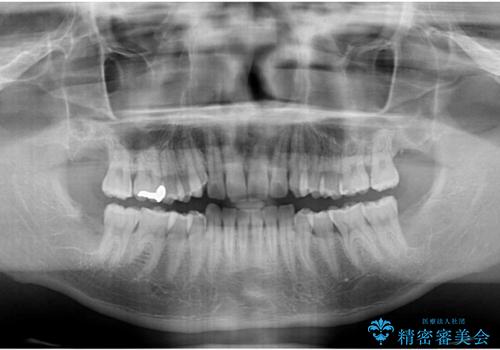

- 前歯のデコボコを気にして来院された患者様です。

当院でインビザライン矯正治療をされている方からのご紹介ということで、インビザラインでの矯正治療をご希望でした。

ワイヤー矯正に比べ来院頻度は低いものの、新幹線での通院のため、やや治療期間が延びることが懸念されました。

配属異動や長時間勤務などによりインビザラインが十分に装着できない期間があり、インビザライン有効期限5年間ギリギリとなってしまいました。